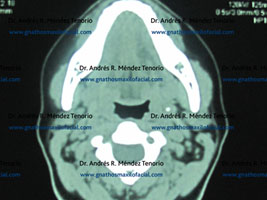

Tomografías computarizadas antes y después del procedimiento quirúrgico